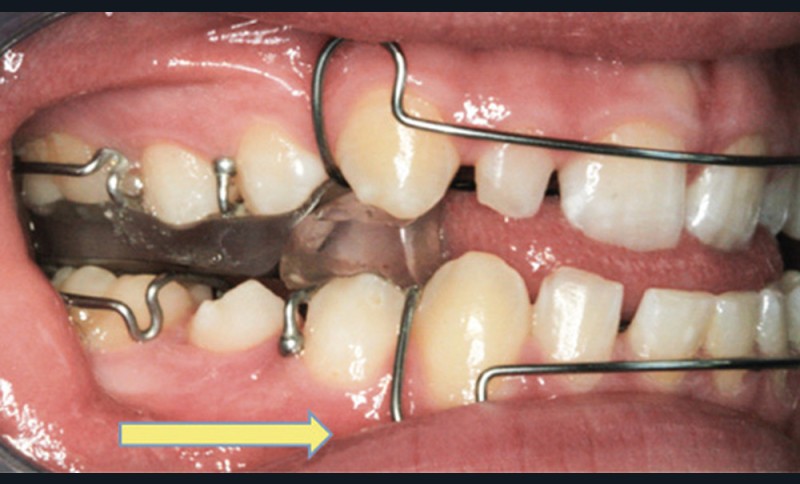

On évalue également la forme générale des arcades dentaires, les signes d’encombrement, l’occlusion dans les trois dimensions de l’espace ainsi que la posture et la mobilité linguale. Une classe II dentaire marquée, une constriction du maxillaire (endoalvéolie ou endognathie associées ou non à un articulé croisé postérieur) ainsi qu’une béance antérieure sont des signes d’appels de Sahos [8] (fig. 7). Une triade intra-orale évocatrice est souvent présente chez ces enfants : palais étroit et profond, troubles de la posture linguale (macroglossie, frein lingual court, etc.) et Hypertrophie amygdalienne (HTA) [5].

L’expansion maxillaire rapide

Les enfants apnéiques présentent souvent une insuffisance de croissance transversale du maxillaire. L’Expansion maxillaire rapide (EMR) chez les enfants en cours de croissance, par la disjonction de la suture médio-palatine, permet de corriger cette anomalie ainsi que l’encombrement dentaire associé (fig. 9). C’est une technique largement utilisée, bien acceptée par les patients et qui facilite la prise en charge ultérieure des autres anomalies orthodontiques, notamment de la dimension antéropostérieure.

C’est une thérapeutique de choix chez les enfants atteints de Sahos : elle améliorerait la qualité du sommeil à court et long terme par l’augmentation du volume des VAS (au niveau du palais et des fosses nasales) [25-26-27-28]. L’EMR, par l’élargissement du maxillaire, crée un espace suffisant pour la langue, favorisant sa position haute. Une ascension de l’os hyoïde, associée à ce changement de posture linguale après l’expansion maxillaire rapide, a été mise en évidence dans la littérature [27-29-30]. Au cours de la croissance, l’EMR pourrait s’inscrire dans un traitement orthodontique global qui vise à corriger également les sens antéropostérieur ou vertical. Enfin, et malgré son efficacité, cette thérapeutique peut ne pas traiter complètement certains patients chez qui les symptômes de Sahos ne s’améliorent pas (Villa, 2015, Guilleminault, 2011). Dans ce cas-là, des traitements orthodontico-chirurgicaux seront alors indiqués.